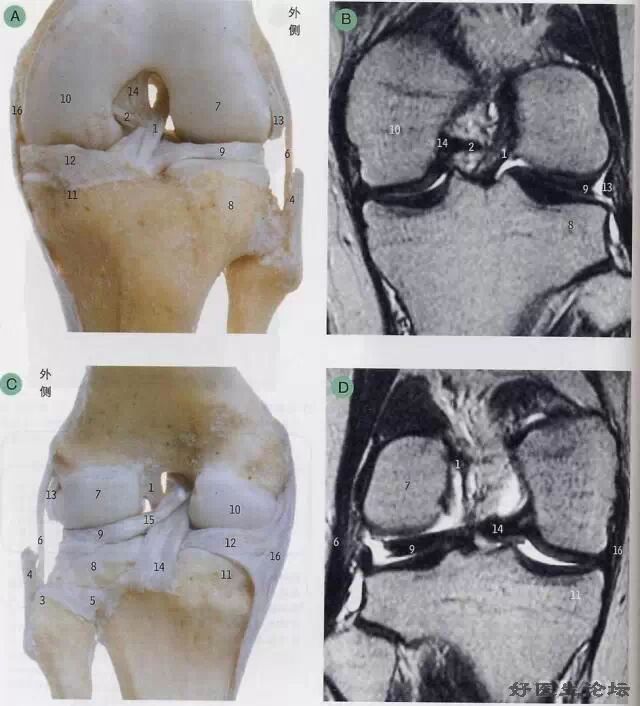

影像学检查

* MRI

MRI